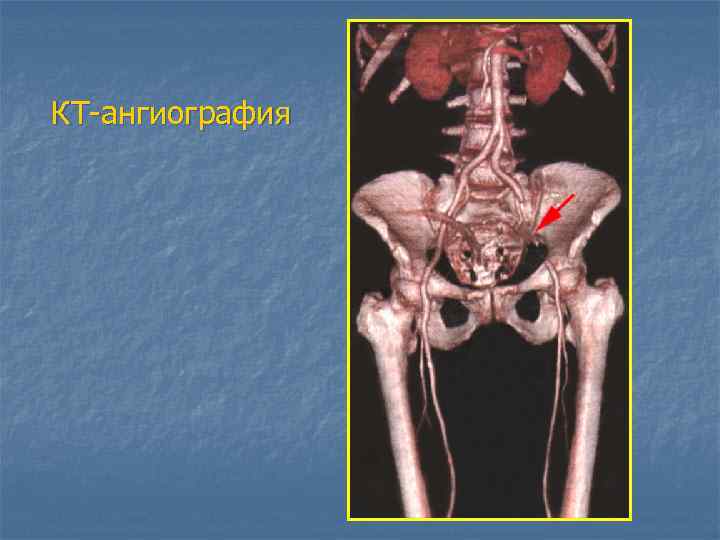

КТ-ангиография